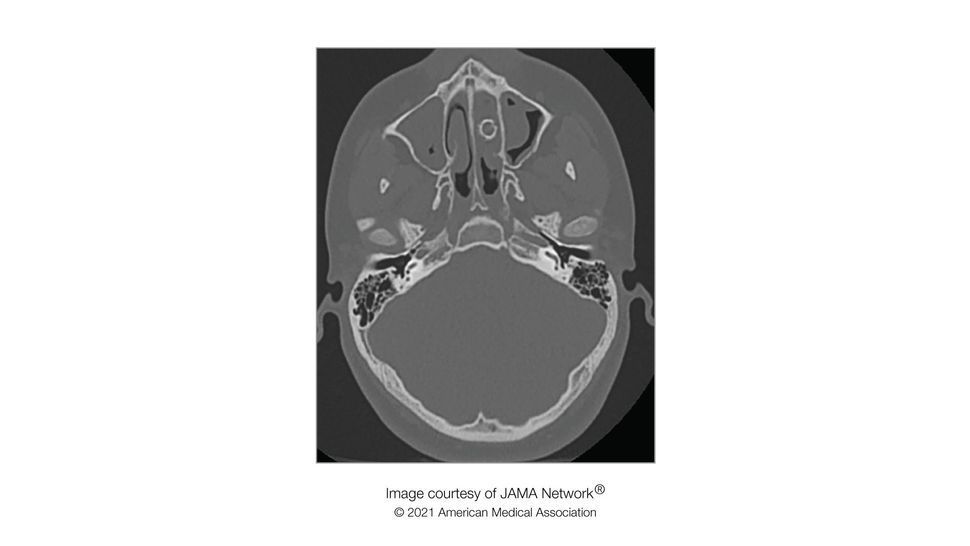

A teen unknowingly had a BB pellet lodged in his nose for eight years, which caused a "foul odor" when he blew his nose. The teen first visited doctors for his symptoms when he was 15 years old, Live Science previously reported. By that point, he had experienced nasal congestion for several years along with a reduced sense of smell, according to a report of the case, published Feb. 18 in the journal JAMA Otolaryngology–Head & Neck Surgery. At first, he received a nasal spray and antihistamine medication for his symptoms. But when he returned to the doctor a year later, the authors noticed "a pungent, foul odor" that filled the room when he blew his nose. A CT scan showed a 0.35-inch (9 millimeters) spherical structure in his nasal cavity. The teen underwent surgery to remove the object, which turned out to be a metallic BB pellet. A talk with the teen's family revealed that he had been shot in the nose with a pellet gun when he was about 8 or 9 years old. At the time, the boy hadn't experienced symptoms, so his parents had not sought medical care. The pellet had been hard to spot at first because new tissue had grown over it. It had blocked the drainage pathways in the boy's nose, which led to a buildup of mucus, debris and bacteria that in turn caused the foul odor, the authors said. After the boy's surgery, the unpleasant odor disappeared.